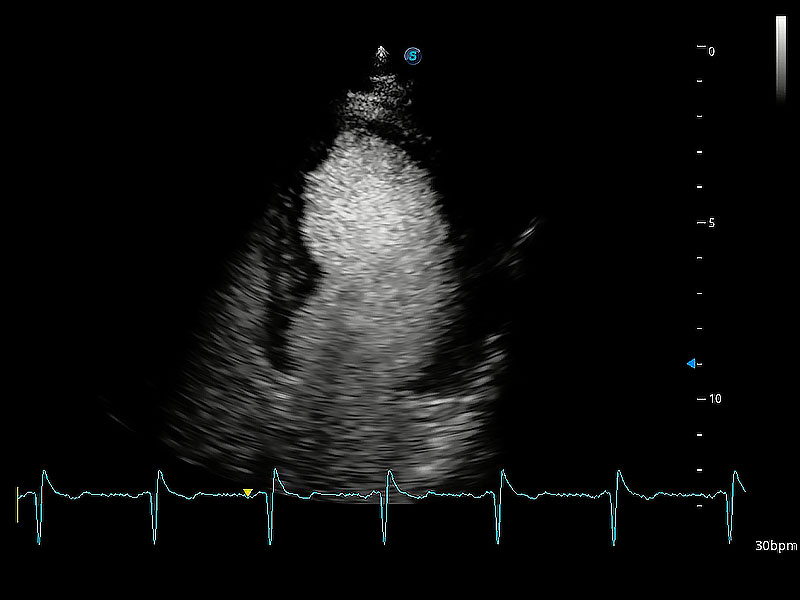

ProPet 80 配備了豐富的心臟探頭群、先進的成像技術(shù)和專業(yè)的心臟測量工具,可幫助動物醫(yī)生為不同體型和生理結(jié)構(gòu)的動物提供心臟和心肌功能的全面評估。

通過360度任意調(diào)節(jié)3條M型取樣線,在同一心動周期上觀察心臟不同位置的運動曲線,得到準確的心功能測量數(shù)據(jù),有效評估心肌運動及左心室功能。